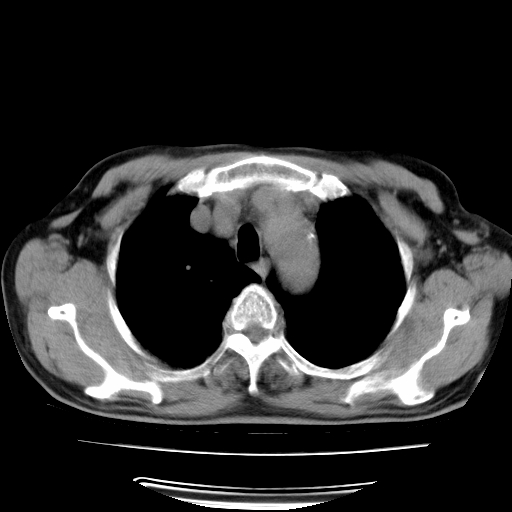

男,71岁,咳嗽,气喘10年,再发并咯血.胸片见气胸

考虑  左肺中心型肺癌伴阻塞性肺炎,肺不张,纵膈淋巴结肿大。慢支炎,肺气肿,左侧气胸肺压缩5%

左侧中央型肺癌伴纵膈淋巴结转移。

左肺中心型肺癌伴阻塞性肺炎,肺不张,纵膈淋巴结肿大

1)考虑左肺中心型肺癌伴阻塞性肺炎、左肺下叶肺不张、左侧肺气肿,纵膈淋巴结转移。2)左侧气胸(肺组织压缩约5%)。

左肺中心型肺癌伴阻塞性肺不张、肺气肿 。

1)考虑左肺中心型肺癌伴阻塞性肺炎、左肺下叶肺不张、左侧肺气肿,纵膈淋巴结转移。2)左侧气胸。